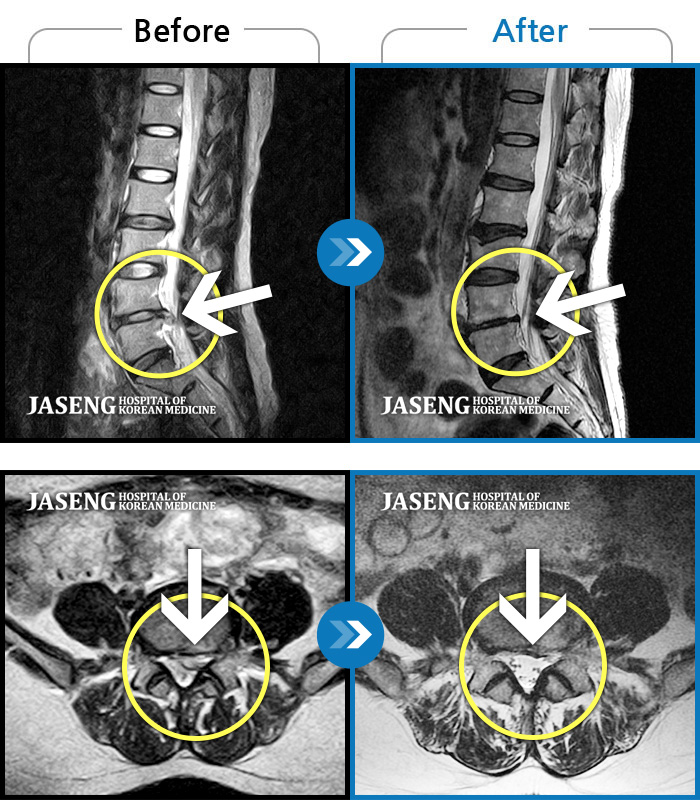

허리디스크

수원 · 김태성 원장

우측 허리 통증과 우측 다리 방사통으로 활동하기 힘든 상태

촬영시기

2021.02.03 ~ 2021.07.09

2022.03.25

조회수 248